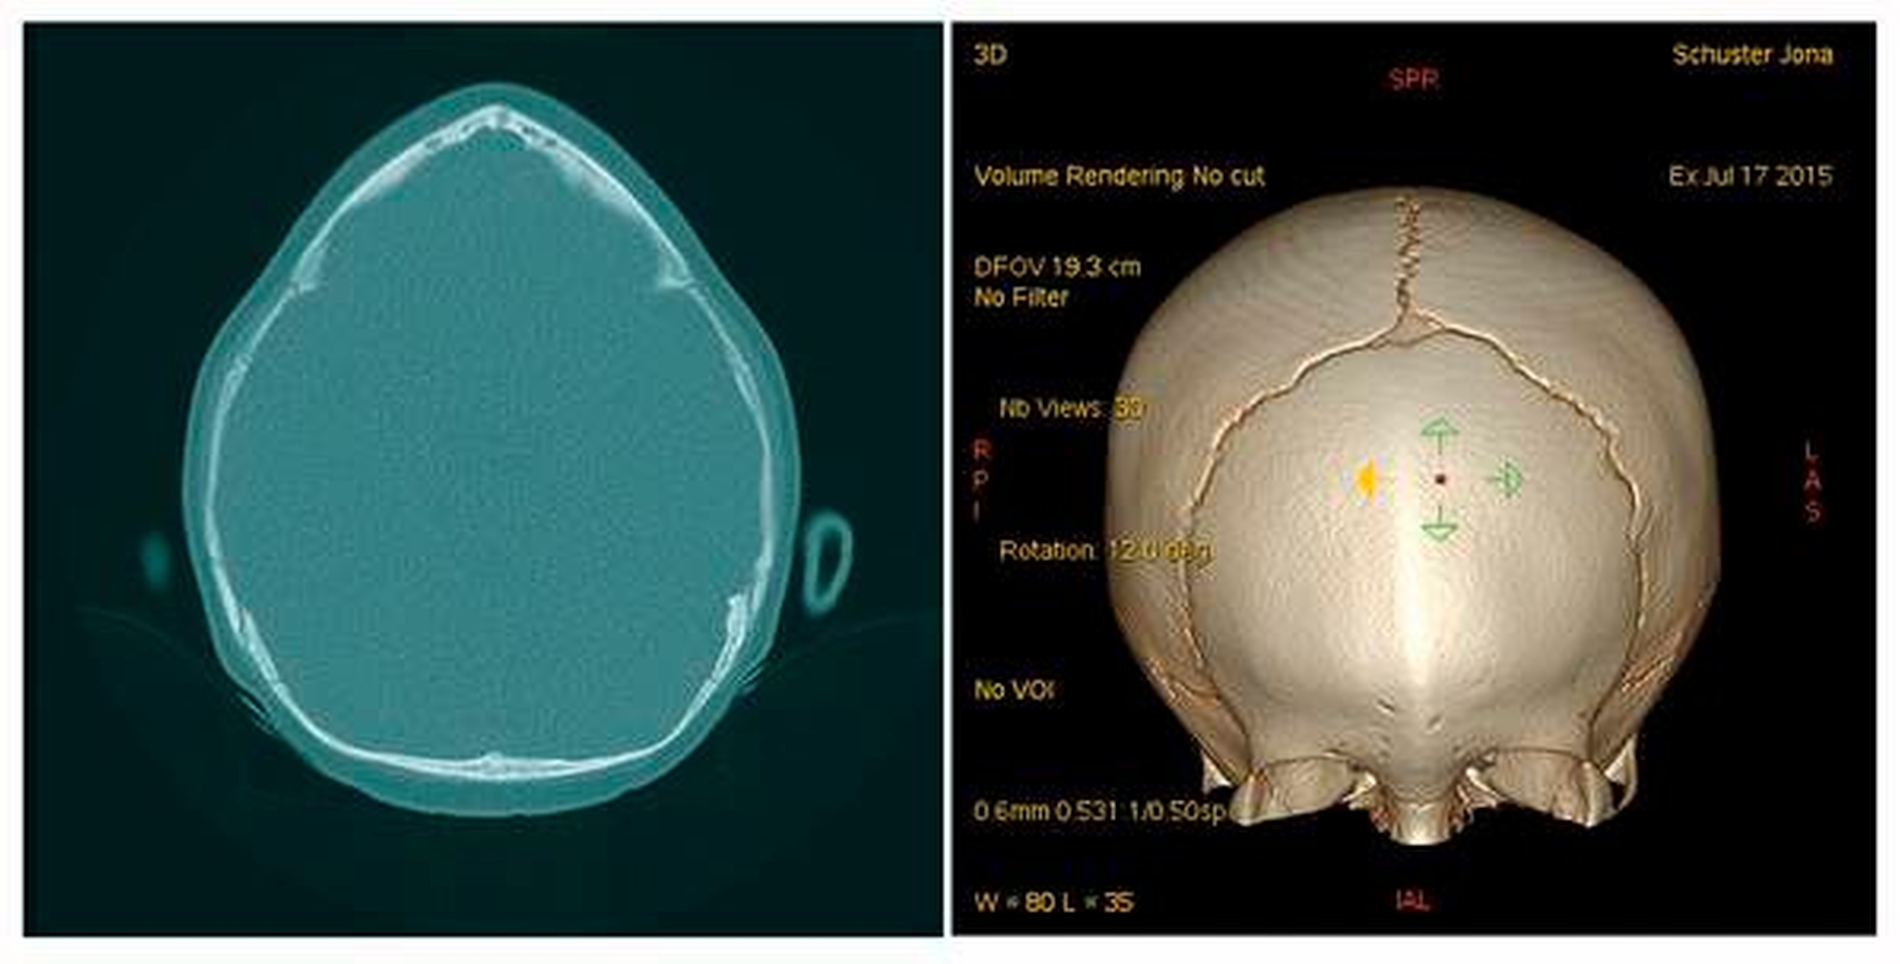

Zur Diagnostik veranlassten wir bei dem jungen Patienten eine MRT sowie eine Spiral-CT des Schädels unter Narkose. Diese ergaben eine unauffällige Darstellung des Neurokraniums, ohne Hinweise auf eine Liquorzirkulationsstörung. Zudem zeigte sich eine symmetrische Kopfform, wobei sich die Frontalnaht vorzeitig verknöchert darstellte und sich nicht abgrenzte (Zustand nach vorzeitigem Verschluss der Sutura frontalis). Es bestand keine Optikuskompression. Die übrigen Schädelwachstumsnähte, insbesondere die Sagittalnaht und die Lambdanaht, waren regelrecht. Außerdem lag eine regelrechte offene Darstellung der Schädelbasis vor (Abbildung 2). Zur Identifizierung von chromosomal bedingten syndromalen Erkrankungen erfolgte die Vorstellung in der humangenetischen Sprechstunde unserer Klinik. Daraufhin konnte das Krankheitsbild einer syndromalen Kraniosynostose ausgeschlossen werden.

Wie im vorliegenden Fall beschrieben, entwickelt sich aufgrund der vorzeitigen Verknöcherung eine keilförmige Aufwulstung der Stirnmitte, die zu einer Art Knochenleiste führt. Durch die gleichzeitige Abflachung der frontolateralen Region kommt es zur typischen dreieckigen Schädelform (Abbildung 2). Das Gesamtbild ist durch eine schmale hohe Stirn mit einem verbreitert wirkenden Hinterkopf geprägt [Freudlsperger et al., 2018]. Bei der syndromalen Kraniosynostose handelt es sich um eine Differenzierungsform mit vielen unterschiedlichen Ausprägungen.